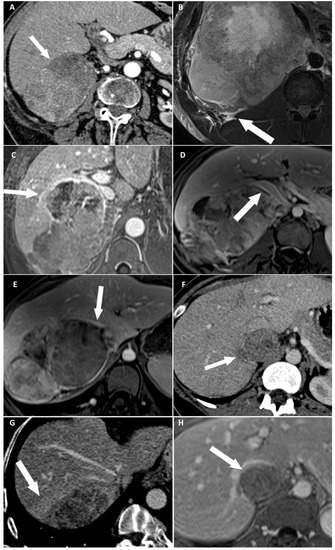

| Disappearance of fat border between ACC and liver | Portal phase CT T2 HASTE MRI (**) | Fat border between ACC and liver non-measurable (<1 mm) |

| Periadrenal fat densification | Portal phase CT T2 FSE MRI | ΔHU between periadrenal fat and normal retroperitoneal fat >10 HU Hyperintense areas in the periadrenal fat |

| ACC contour disruption | Portal phase CT Portal phase MRI | Measurable adrenal capsular defect without any enhancement |

| Macroscopic mass effect on inferior vena cava | Portal phase CT Portal phase MRI | Intrahepatic displacement of the vessel and direct contact with the tumor ± changes of its caliber |

| Macroscopic mass effect on right hepatic vein | Portal phase CT Portal phase MRI | Intrahepatic displacement of the vessel and direct contact with the tumor ± changes of its caliber |

| Focal ACC bulge | Portal phase CT Portal phase MRI | Focal and abrupt irregularity of ACC shape |

| Periadrenal hepatic parenchyma enhancement | Portal phase CT | ΔHU > 20 HU between periadrenal liver parenchyma and normal adjacent parenchyma |

| ACC inclusion by hepatic parenchyma > 180° | Portal phase CT Portal phase MRI | ACC surrounded by the liver parenchyma over its half-circumference |